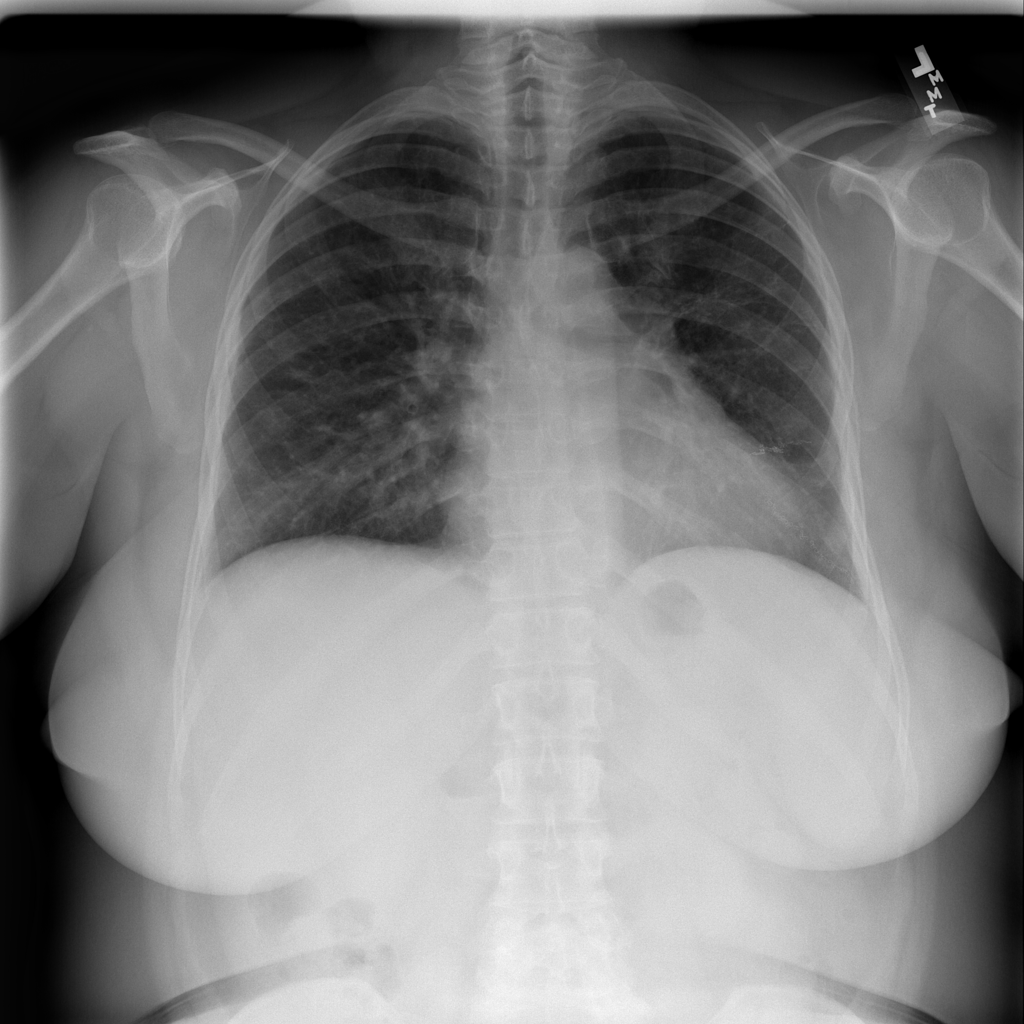

Showing up to 90 reference images for Pneumothorax.

PAT-4639 · IMG-013Pneumothorax

PAT-4639 · IMG-013

AP